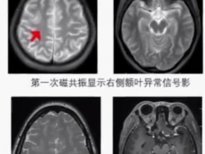

Çin'de 23 yaşındaki ismi Chen olarak açıklanan genç, beyninde canlı kurtçukla 17 yıl yaşadı. Altı yaşından itibaren el ve ayaklarında uyuşukluk hisseden Chen, vücudunun üst sağ kısmındaki hislerini kaybedince doktora gitti.